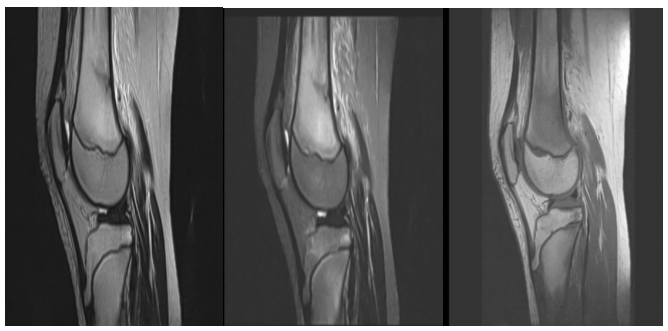

图3:与图1、图2为同一患者。T1WI显示股骨远端及胫骨近端斑点状、斑片状低信号,T2WI及其抑脂序列显示股骨远端与胫骨近端斑点状、斑片状高信号,股骨远端见带状低信号,与X线及CT检查显示带状高密度区域向对应,提示股骨远端与胫骨近端骨髓水肿、股骨远端应力性骨折。